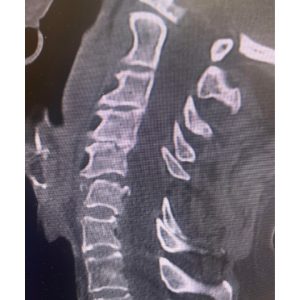

The first 2 pictures are a CT scan and then an MRI of the C5-6 fracture with spinal cord compression. The next is X-ray taken during surgery. The last is X-ray at 2 months postoperative. At 2 months after surgery, the patient is living at home again. She is as strong as ever!”